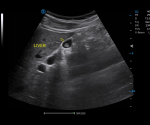

Upgraded Image Quality with Advanced Technology

· Pixel Echo Zone improves image uniformity

· Tailored Filter enhance S/N ratio to achieve higher image contrast

· S-Beam avoids image distortion

· Raw Data Processing enables flexible image adjustment